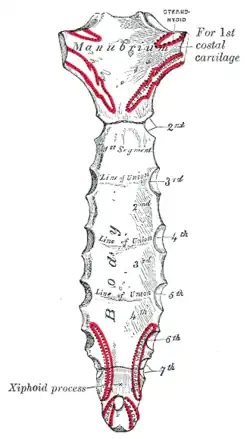

Le processus xiphoïde (ou apophyse xiphoïde ou appendice xiphoïde ou appendice ensiforme ou pointe du sternum ou processus ensiforme ou xiphisternum)[1],[2], est une structure osseuse ou cartilagineuse qui se situe à la partie inférieure du sternum.

Le processus xiphoïde est relié à la base du corps du sternum par la synchondrose xipho-sternale et se projette au niveau de la dixième vertèbre thoracique (T10).

Il est de forme triangulaire avec sa base reliée au corps du sternum.

En haut des bords latéraux se trouvent deux échancrures qui contribuent avec leurs répondantes du corps du sternum à former les septièmes incisures costales du sternum.